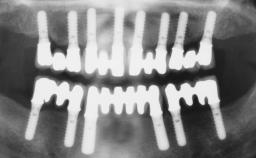

# of Implants 6

Type of Implants One-Piece

Defining Characteristics Fully edentulous lower jaw to be rehabilitated with two or more implants

Modality > 4 implants, extending to mental nerve region

Bone Volume Horizontally and vertically sufficient